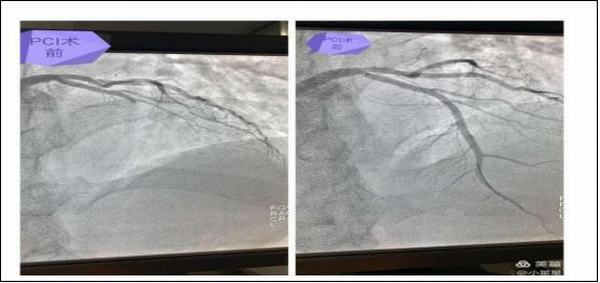

15分鐘后,患者王先生在家屬的陪同下來(lái)到了延安大學(xué)咸陽(yáng)醫(yī)院心血管病院11樓心六科,在吳醫(yī)生問(wèn)診及查體時(shí)患者胸痛再次發(fā)作,并于4點(diǎn)20分突然出現(xiàn)四肢抽搐、呼之不應(yīng),觸摸頸動(dòng)脈搏動(dòng)消失,呼吸呈嘆息樣,立即予以心肺復(fù)蘇術(shù),心電監(jiān)測(cè)提示心室停搏,與此同時(shí)我科楊登魁責(zé)任總醫(yī)師、我院心一科王銀濤醫(yī)師、心二科代雪茹醫(yī)師、心三科王巖醫(yī)師、留夜護(hù)士陳娜、心七科徐云鵬醫(yī)師、留夜護(hù)士高謙聞?dòng)嵹s來(lái),并立即投入緊張的搶救過(guò)程中,經(jīng)予持續(xù)胸外按壓、多次電除顫等治療后患者于4點(diǎn)40分意識(shí)逐漸恢復(fù),心電監(jiān)測(cè)示加速性室性自主心律,搶救成功,而早己就位的導(dǎo)管室同仁也做好了準(zhǔn)備工作,并于6點(diǎn)40分成功開通了患者閉塞血管,術(shù)后患者生命體征平穩(wěn)。